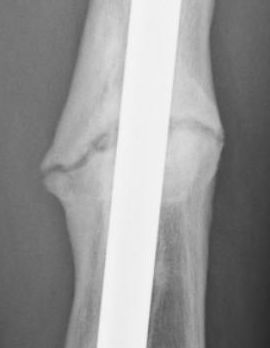

Jan. 31, 2006 Aug. 17, 2006 Apr. 17, 2007 Feb. 21, 2008